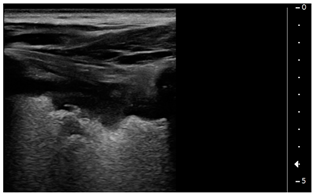

![]() | PATTERN 4 Broken pleural line with subpleural consolidations <1 cm |

![]() | PATTERN 5 Consolidation >1 cm without pleural effusion |